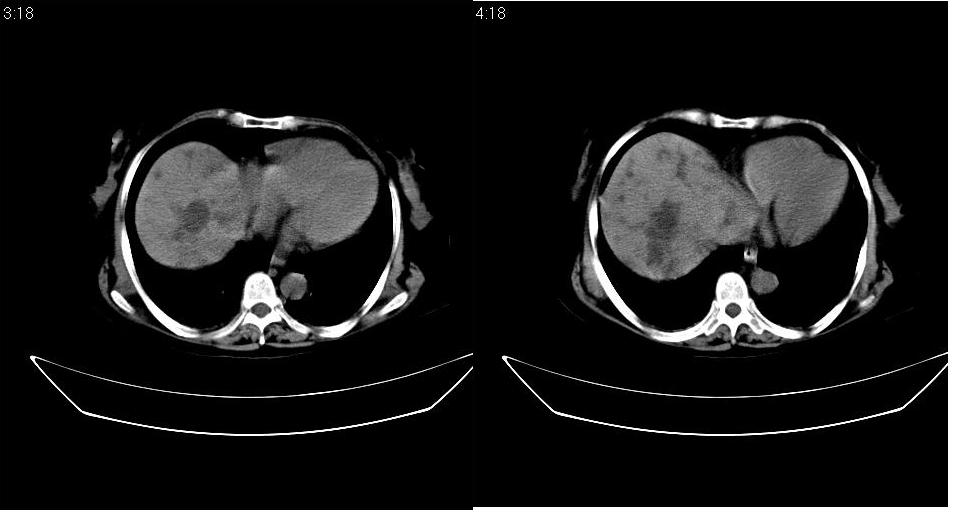

以下是引用守望可可西里在2007-1-20 23:09:00的发言:[br][br] 胰头癌,胆总管梗阻、截断,肝内外胆管重度扩张,肝内边缘部分的圆形低密度病灶多能与扩张的胆管较为连续,暂不考虑转移。病人没有黄疸吗?

以下是引用天南地北在2007-1-20 23:22:00的发言:[br]1:按照肿块的位置及胆总管的形态:考虑胆总管(中下段)癌并肝内胆管扩张,累及胰头。2:不排除胰头癌并肝内胆管扩张。[br]肝内病灶看起来还是扩张的胆管,不考虑转移先。